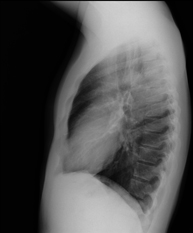

- Tórax

- RX Tórax

Técnica mediante la cual, utilizando rayos X, se obtienen imágenes de la caja torácica (corazón, pulmones, arcos costales, clavículas, etc.) para su estudio.

Una radiografía de tórax es una técnica mediante la cual, utilizando una pequeña dosis de radiación, se obtiene una imagen bidimensional de la caja torácica y su contenido (pulmones, corazón, mediastino, etc.). Es una de las pruebas médicas más comúnmente realizadas.